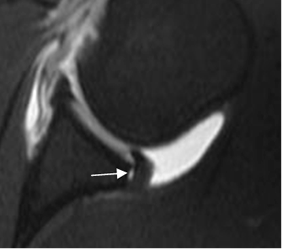

Fig 73 B. Lesión POLSA.

ArtroRM axial en STIR. Defecto en el labrum posterior, el cual se llena de contraste y sin ruptura del periostio, por lesión POLSA.